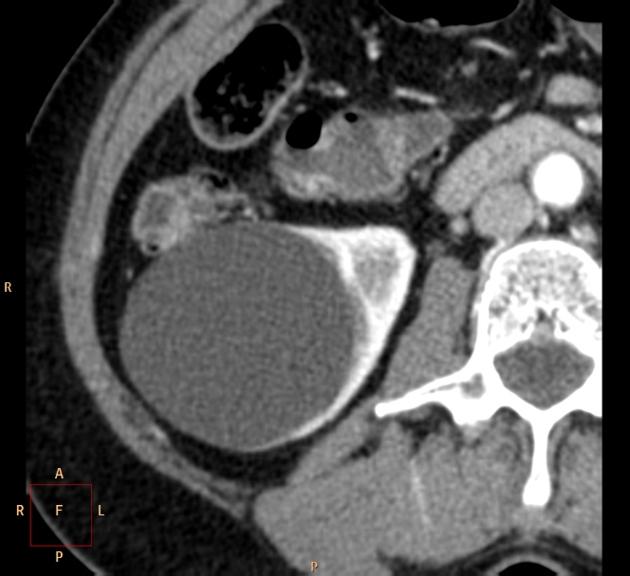

Bosniak sınıflandırması genellikle kontrastlı bilgisayarlı tomografi (BT) ile yapılır. Ancak son yıllarda manyetik rezonans görüntüleme (MRI) ve kontrastlı ultrason (CEUS) gibi yeni teknikler de tanıda etkin biçimde kullanılmaktadır.

BT (Bilgisayarlı Tomografi)

- Sınıflamanın altın standardıdır.

- Kontrastlı BT ile septa, kalsifikasyon ve nodül tespiti mümkündür.

Bosniak Sınıf IV: Malignite Şüphesi En Yüksek Olan Kistler

- Sınıf III özelliklerine ek olarak, içerisinde solid (katı) komponentler veya nodüller bulunur.

- Bu yapıların tamamı kontrast madde tutar.

- Kanser riski %85–100 aralığındadır.

- Tedavi genellikle cerrahidir.